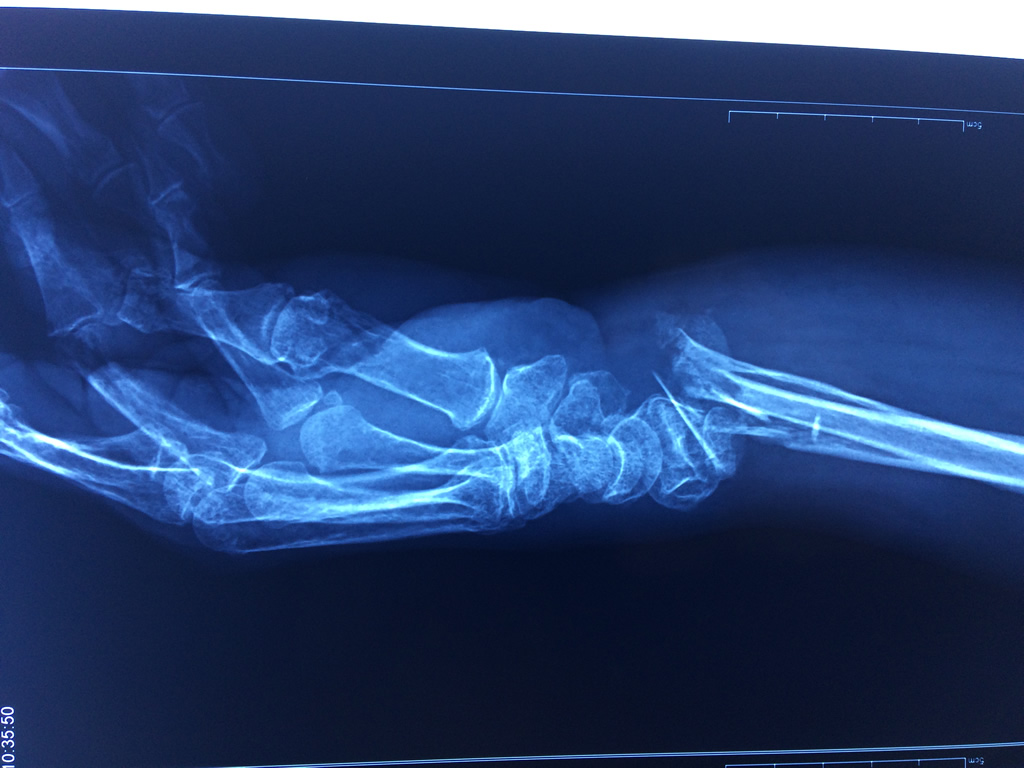

Los procedimientos más comunes en cirugía de la mano son aquellos destinados a reparar traumatismos, incluyendo lesiones de tendones, nervios, vasos sanguíneos, y articulaciones; huesos fracturados; y quemaduras, cortes, y otros daños de la piel.